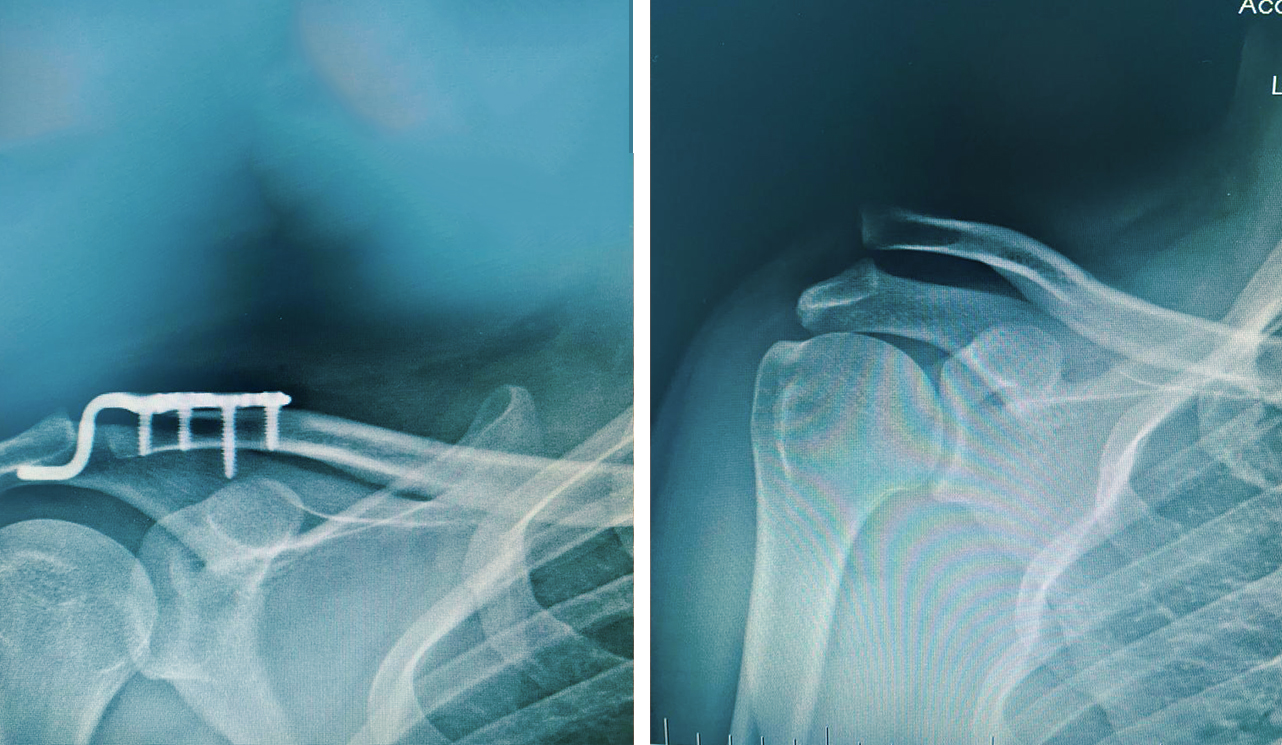

Ortopedik cerrahinin bir alt uzmanlığı olarak kabul edilir ve kırık kemiklerin tedavi edilmesine ve vücudun yaralı kısmının yaralanmadan önce sahip olduğu orijinal gücüne ve maksimum işlevine geri dönmesini sağlamaya odaklanır.